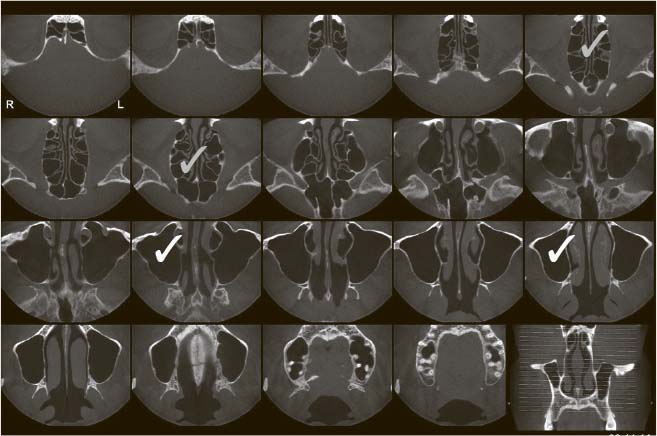

Это рентген 80 lvl. При помощи радиации безболезненно нарезает ваш череп на тоненькие слои (господин Пирогов говорит «Ма-ла-ца!» из мавзолея), по которым можно детально оценить состояние всех структур полости носа, их плотность, характер, взаиморасположение. Незаменимая процедура при хронических риносинуситах: позволяет решить вопрос о необходимости и объеме хирургического лечения. При острых осложненных проблемах дает понять, насколько все плохо.

Компьютерная томограмма придаточных пазух носа, горизонтальная проекция. Белый верхнечелюстные пазухи, серый решетчатый лабиринт

Единственное, чего не может КТ,  помочь в диагностике аденоидов. Да, покажет размер. Но не даст объективной картины. Помимо того, у детей ее применение сомнительно по тем же причинам, что и обычной рентгенографии (в случае острой патологии полости носа).

Компьютерная томограмма придаточных пазух носа, фронтальная проекция